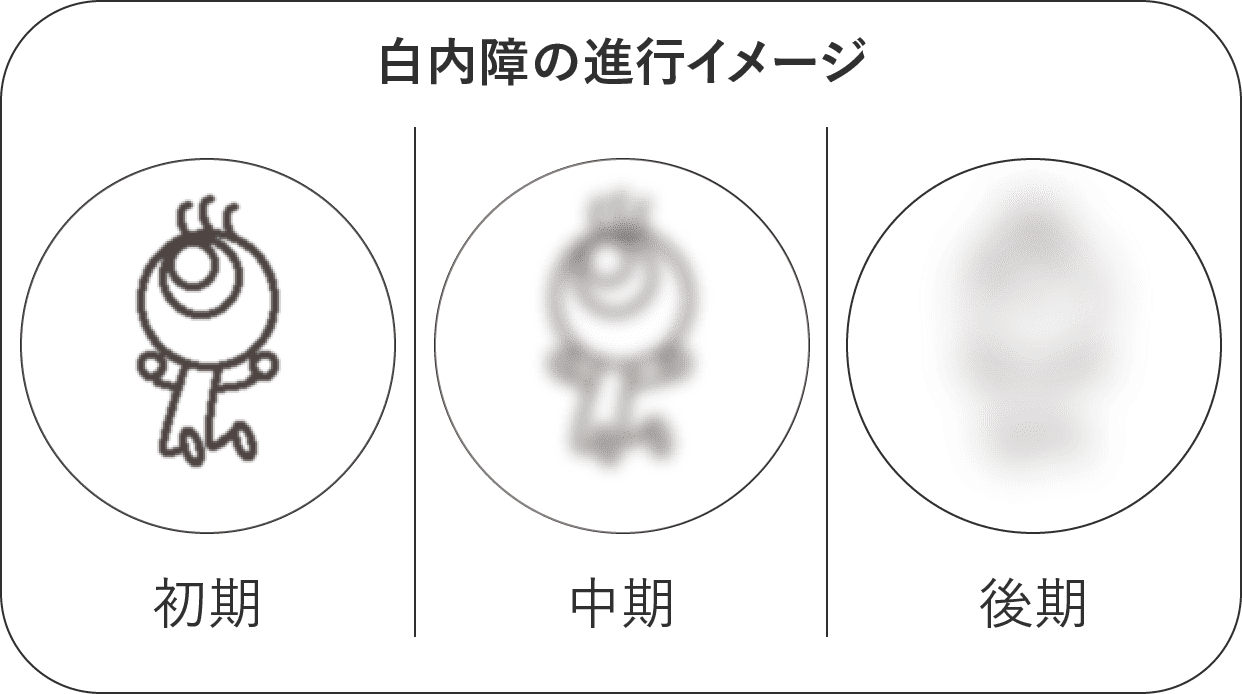

白内障は、目の水晶体が濁ることによって視力が低下する目の病気です。

白内障の症状はゆっくりと進行していき、また初期の症状はわかりにくいため、気づくのが遅くなりがちです。

白内障が進行しすぎると術後の合併症のリスクが高くなるため、ものが見えづらい、眼が疲れやすいなど上記の症状を感じたら、お早めにご相談ください。

じわじわ進行するため早めに気づきにくい

白内障で最も多いのは加齢に伴う老人性白内障です。基本的には両眼性で、比較的緩やかに進行します。

60歳代で70%、70歳代で90%、80歳以上は100%が白内障になります。